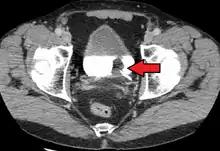

Stage N1 bladder cancer

Lymph nodes in the pelvis. Bladder cancer commonly spreads to obturator and internal iliac (not labelled)